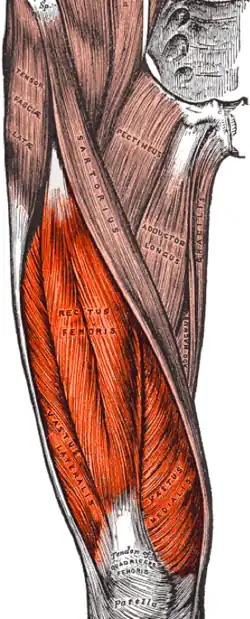

Quadriceps femoris, with different muscles in different colors.

The quadriceps femoris muscle is subdivided into four separate muscles (the 'heads'),[1][2] with the first superficial to the other three over the femur (from the trochanters to the condyles):

- The rectus femoris muscle occupies the middle of the thigh, covering most of the other three quadriceps muscles.[1] It originates on the ilium. It is named for its straight course.

- The vastus lateralis muscle is on the lateral side of the femur (i.e., on the outer side of the thigh).[1]

- The vastus medialis muscle is on the medial side of the femur (i.e., on the inner side of the thigh).[1]

- The vastus intermedius muscle lies between vastus lateralis and vastus medialis on the front of the femur (i.e., on the top or front of the thigh), but deep to the rectus femoris muscle. Typically, it cannot be seen without dissection of the rectus femoris.[1]

The quadriceps forms the bulk of front part of the thigh

The quadriceps forms the bulk of front part of the thigh